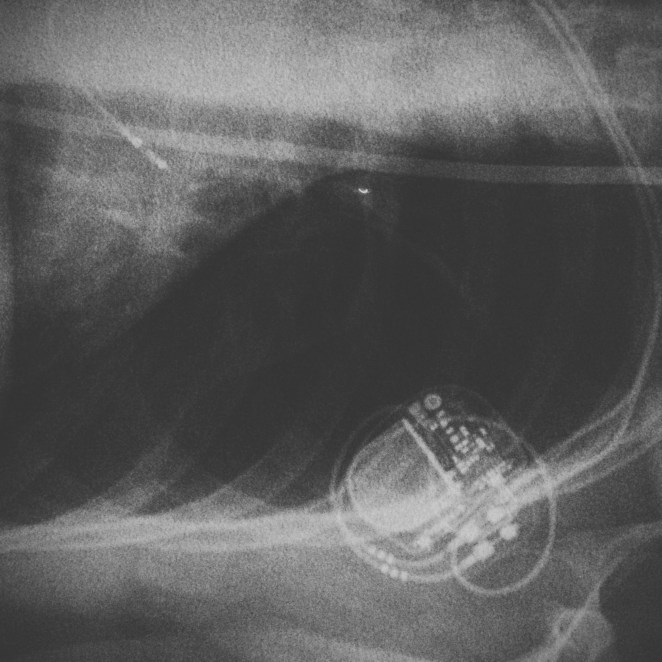

My absence this time is because I had this little box and wires put in my chest last Thursday afternoon. It’s a pacemaker.

The decision was made that I would have a small device implanted into my chest that would constantly monitor my heart. I needed to blackout again. Awesome. Three weeks passed, and in the middle of a doctrine lecture, at exactly 11:31 am, something happened. My heart stopped. Completely. For 5 seconds. We didn’t find this out till a few weeks later, but the problem was worse then we originally thought.

My cardiologist looked at Kirsty and I and said, “Right, we need to get a pacemaker into you as soon as possible”. Plans were then made. Which resulted in last Thursday.